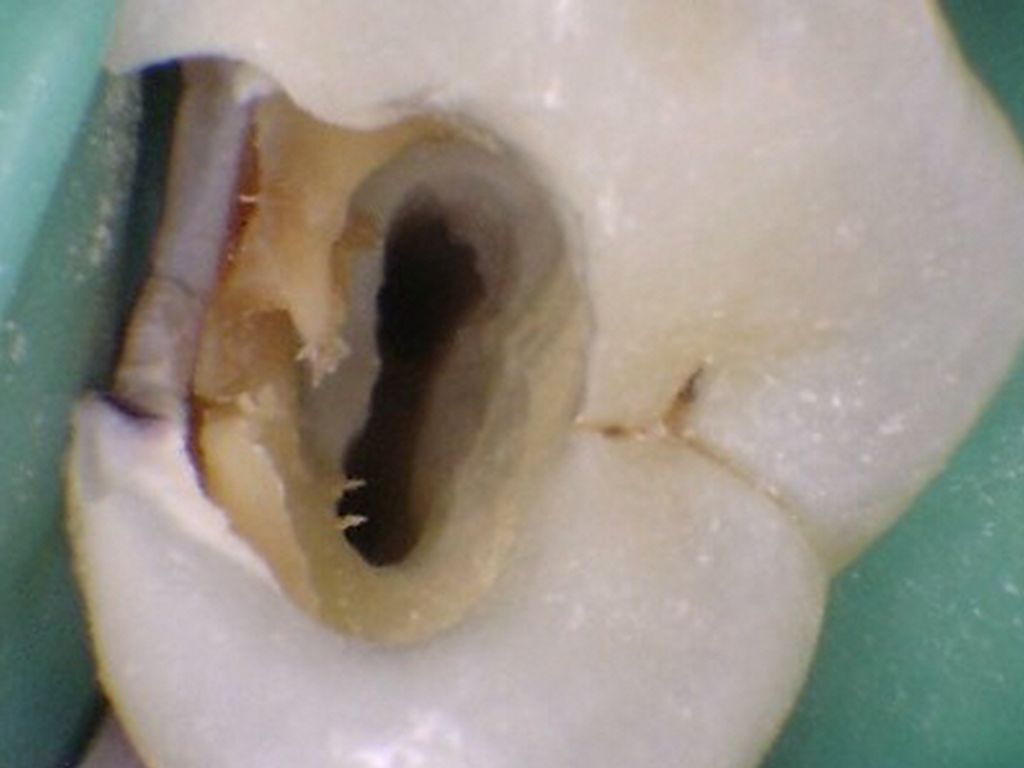

LOCALIZACIÓN DE CONDUCTOS

La entrada de los conductos radiculares SIEMPRE están localizados en la unión de las paredes y el piso

Una vez localizada la unión piso-pared de la cámara pulpar y se haya generado una forma, entonces la entrada de los conductos siempre estará en los vértices de esa forma.